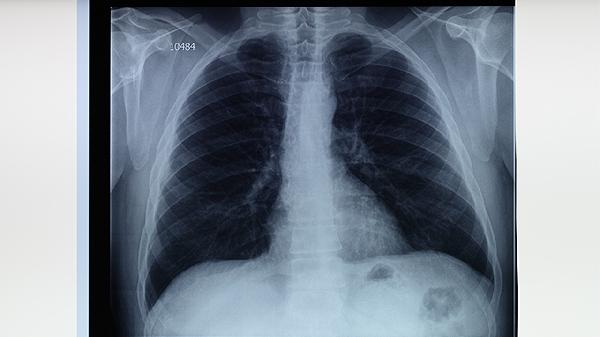

肺结核患者用药需坚持早期、联合、适量、规律、全程原则,疗程通常6-9个月。治疗期间应保持高蛋白饮食如鸡蛋、鱼肉,适当补充维生素B族和维生素C。注意隔离消毒,咳嗽时掩住口鼻,保持居室通风。定期复查胸片和痰菌检查,出现皮疹、黄疸等不良反应及时就医。避免擅自停药导致耐药性产生,家庭成员需同时进行结核菌素试验筛查。